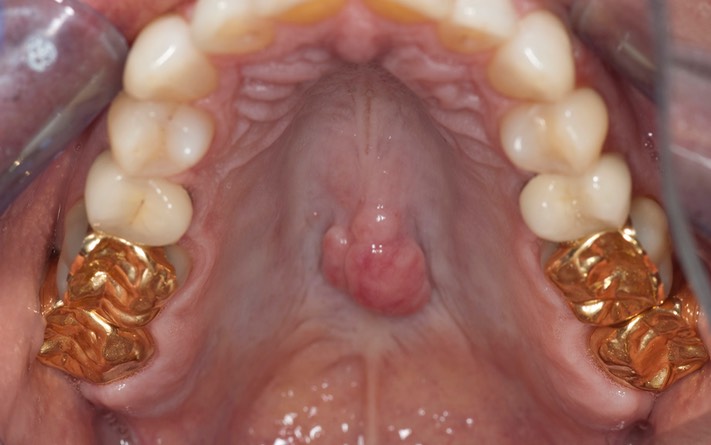

_DSC6148